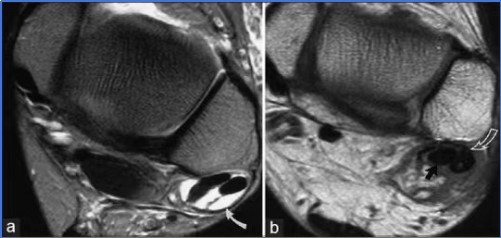

CLAI由于踝关节活动功能的异常,通常会产生滑膜增生、软组织撞击、骨性结构撞击、游离体、软骨损伤以及创伤性关节炎等。

未及时治疗的CLAI可能导致:关节内滑膜增生、骨赘撞击、游离体及软骨损伤,运动功能下降、生活质量降低,研究表明,早期恢复稳定性可有效减少软骨损伤的发生,尤其在运动员群体中更具临床意义。

图14: ab距骨软骨损伤